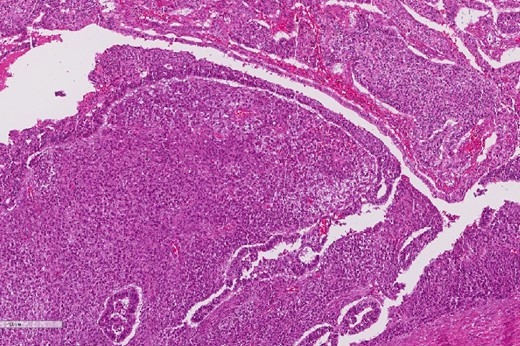

A review of the previously resected esophageal tumor revealed the presence of both epithelial and sarcomatous components. The epithelial component was composed of moderately to poorly differentiated adenocarcinoma, while the sarcomatous component showed hyperchromatic round to spindle cells with scant cytoplasm and frequent mitoses (Figs 3–6). The intrathoracic tumor showed a similar morphology as the sarcomatous component of the esophageal tumor, with focal rhabdomyoblastic differentiation (Fig. 7). The latter was strongly positive for desmin, myogenin, and MyoD1 and was focally positive for synoplastin, CD56, CD 10, and FL1.

Low power magnification of the esophageal tumor exhibiting the epithelial (left) and the sarcomatous components (right).